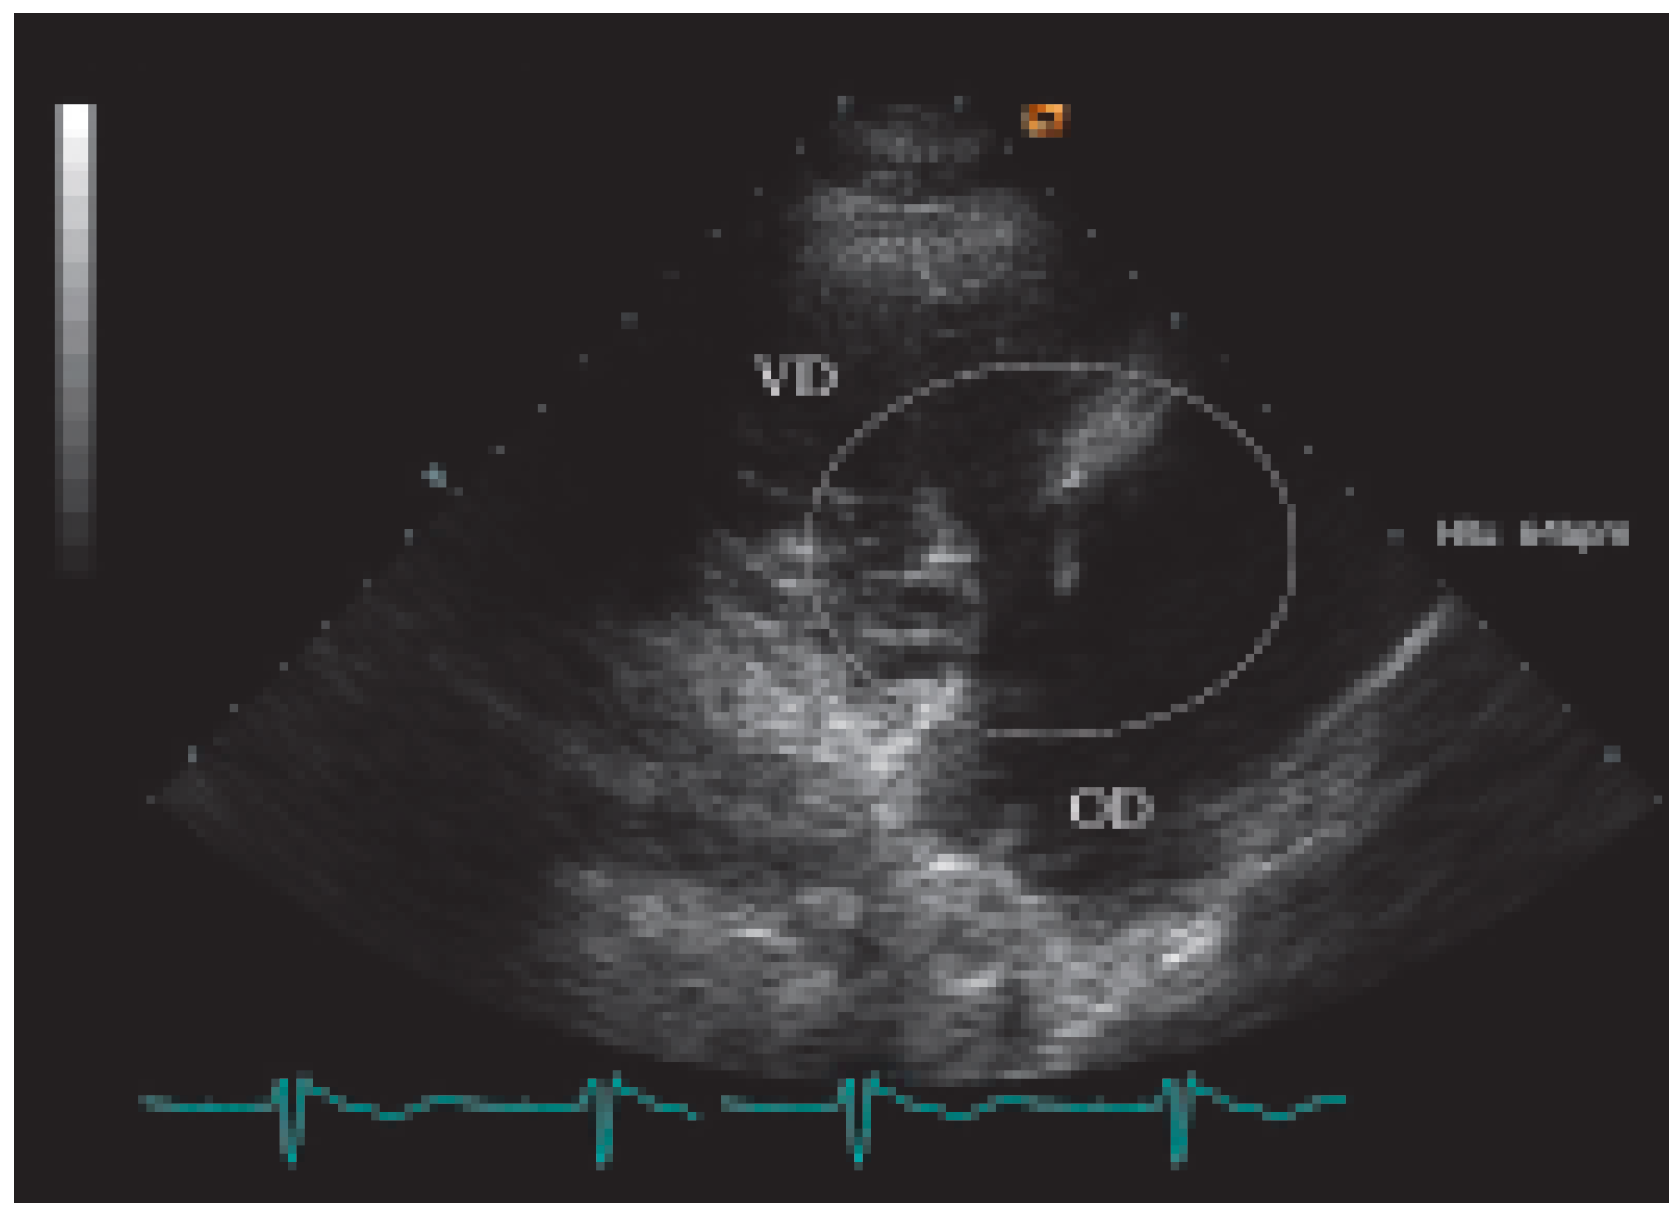

Présentation de cas